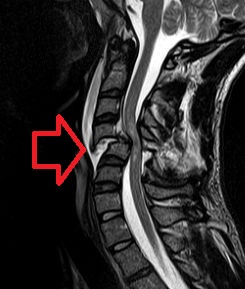

| Cervical spine MRI of a patient with SCI: C4 fracture and dislocation, spinal cord compression |